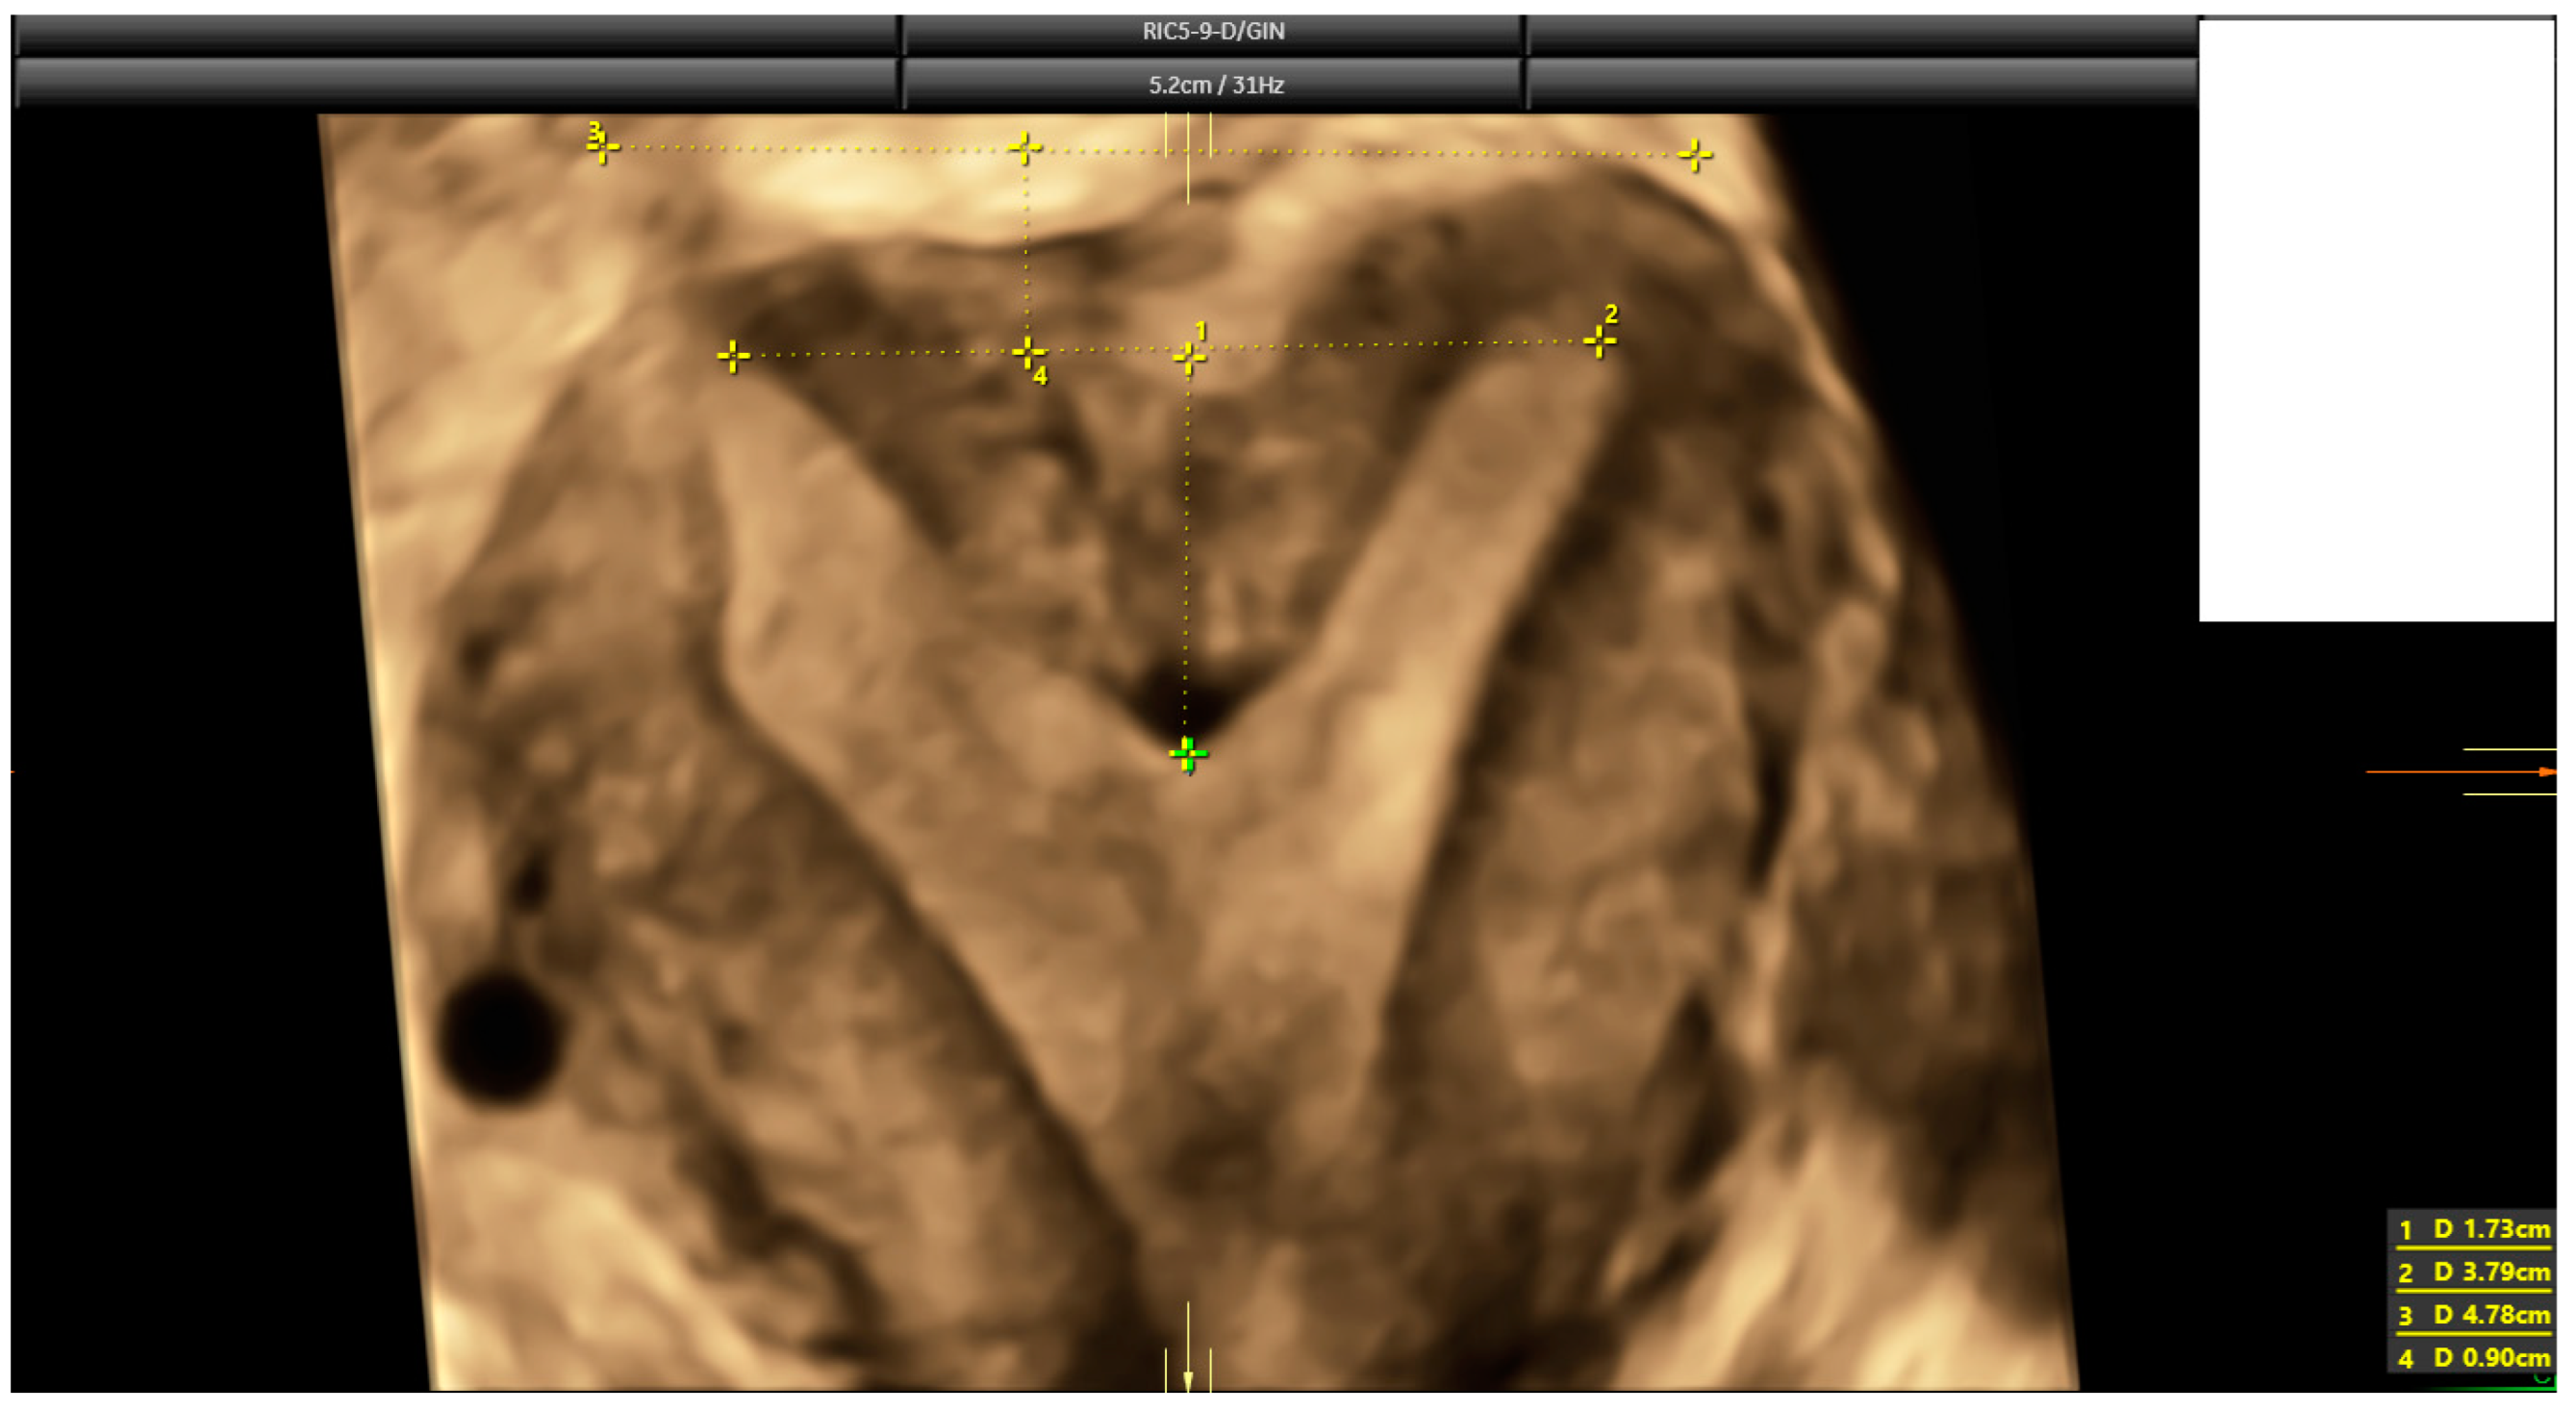

The diagnosis of a septate uterus was determined according to four different criteria (2016-ESHRE-ESGE, 2016-ASRM, 2021-ASRM, and 2019-CUME) [9,12,16] (Figure 2, Figure 3 and Figure 4). The 2016-ASRM classification defines a septate uterus as having a uterine cavity indentation depth >15 mm and an indentation angle <90° [9]. The 2021-ASRM criteria define a septate uterus as having a cavity indentation >10 mm and an indentation angle <90° [10]. The ESHRE-ESGE classification identifies a septate uterus based on an indentation-to-wall-thickness (I:WT) ratio >50% with an external fundal indentation <50% [12]. The CUME criteria specify an indentation in the fundal cavity >10 mm with an external serosal indentation <10 mm [16].

Figure 3.

The same case as Figure 2. According to 2016 and 2021 ASRM criteria, this is a case that falls within the grey zone. Indentation length is 17.3 mm, but indentation angle is 104° (larger than 90°).